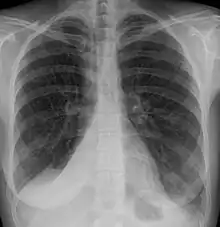

Clinically significant atelectasis is generally visible on chest X-ray; findings can include lung opacification and/or loss of lung volume. Post-surgical atelectasis will be bibasal in pattern. Chest CT or bronchoscopy may be necessary if the cause of atelectasis is not clinically apparent. Direct signs of atelectasis include displacement of interlobar fissures and mobile structures within the thorax, overinflation of the unaffected ipsilateral lobe or contralateral lung, and opacification of the collapsed lobe. In addition to clinically significant findings on chest X-rays, patients may present with indirect signs and symptoms such as elevation of the diaphragm, shifting of the trachea, heart and mediastinum; displacement of the hilus and shifting granulomas.[10]